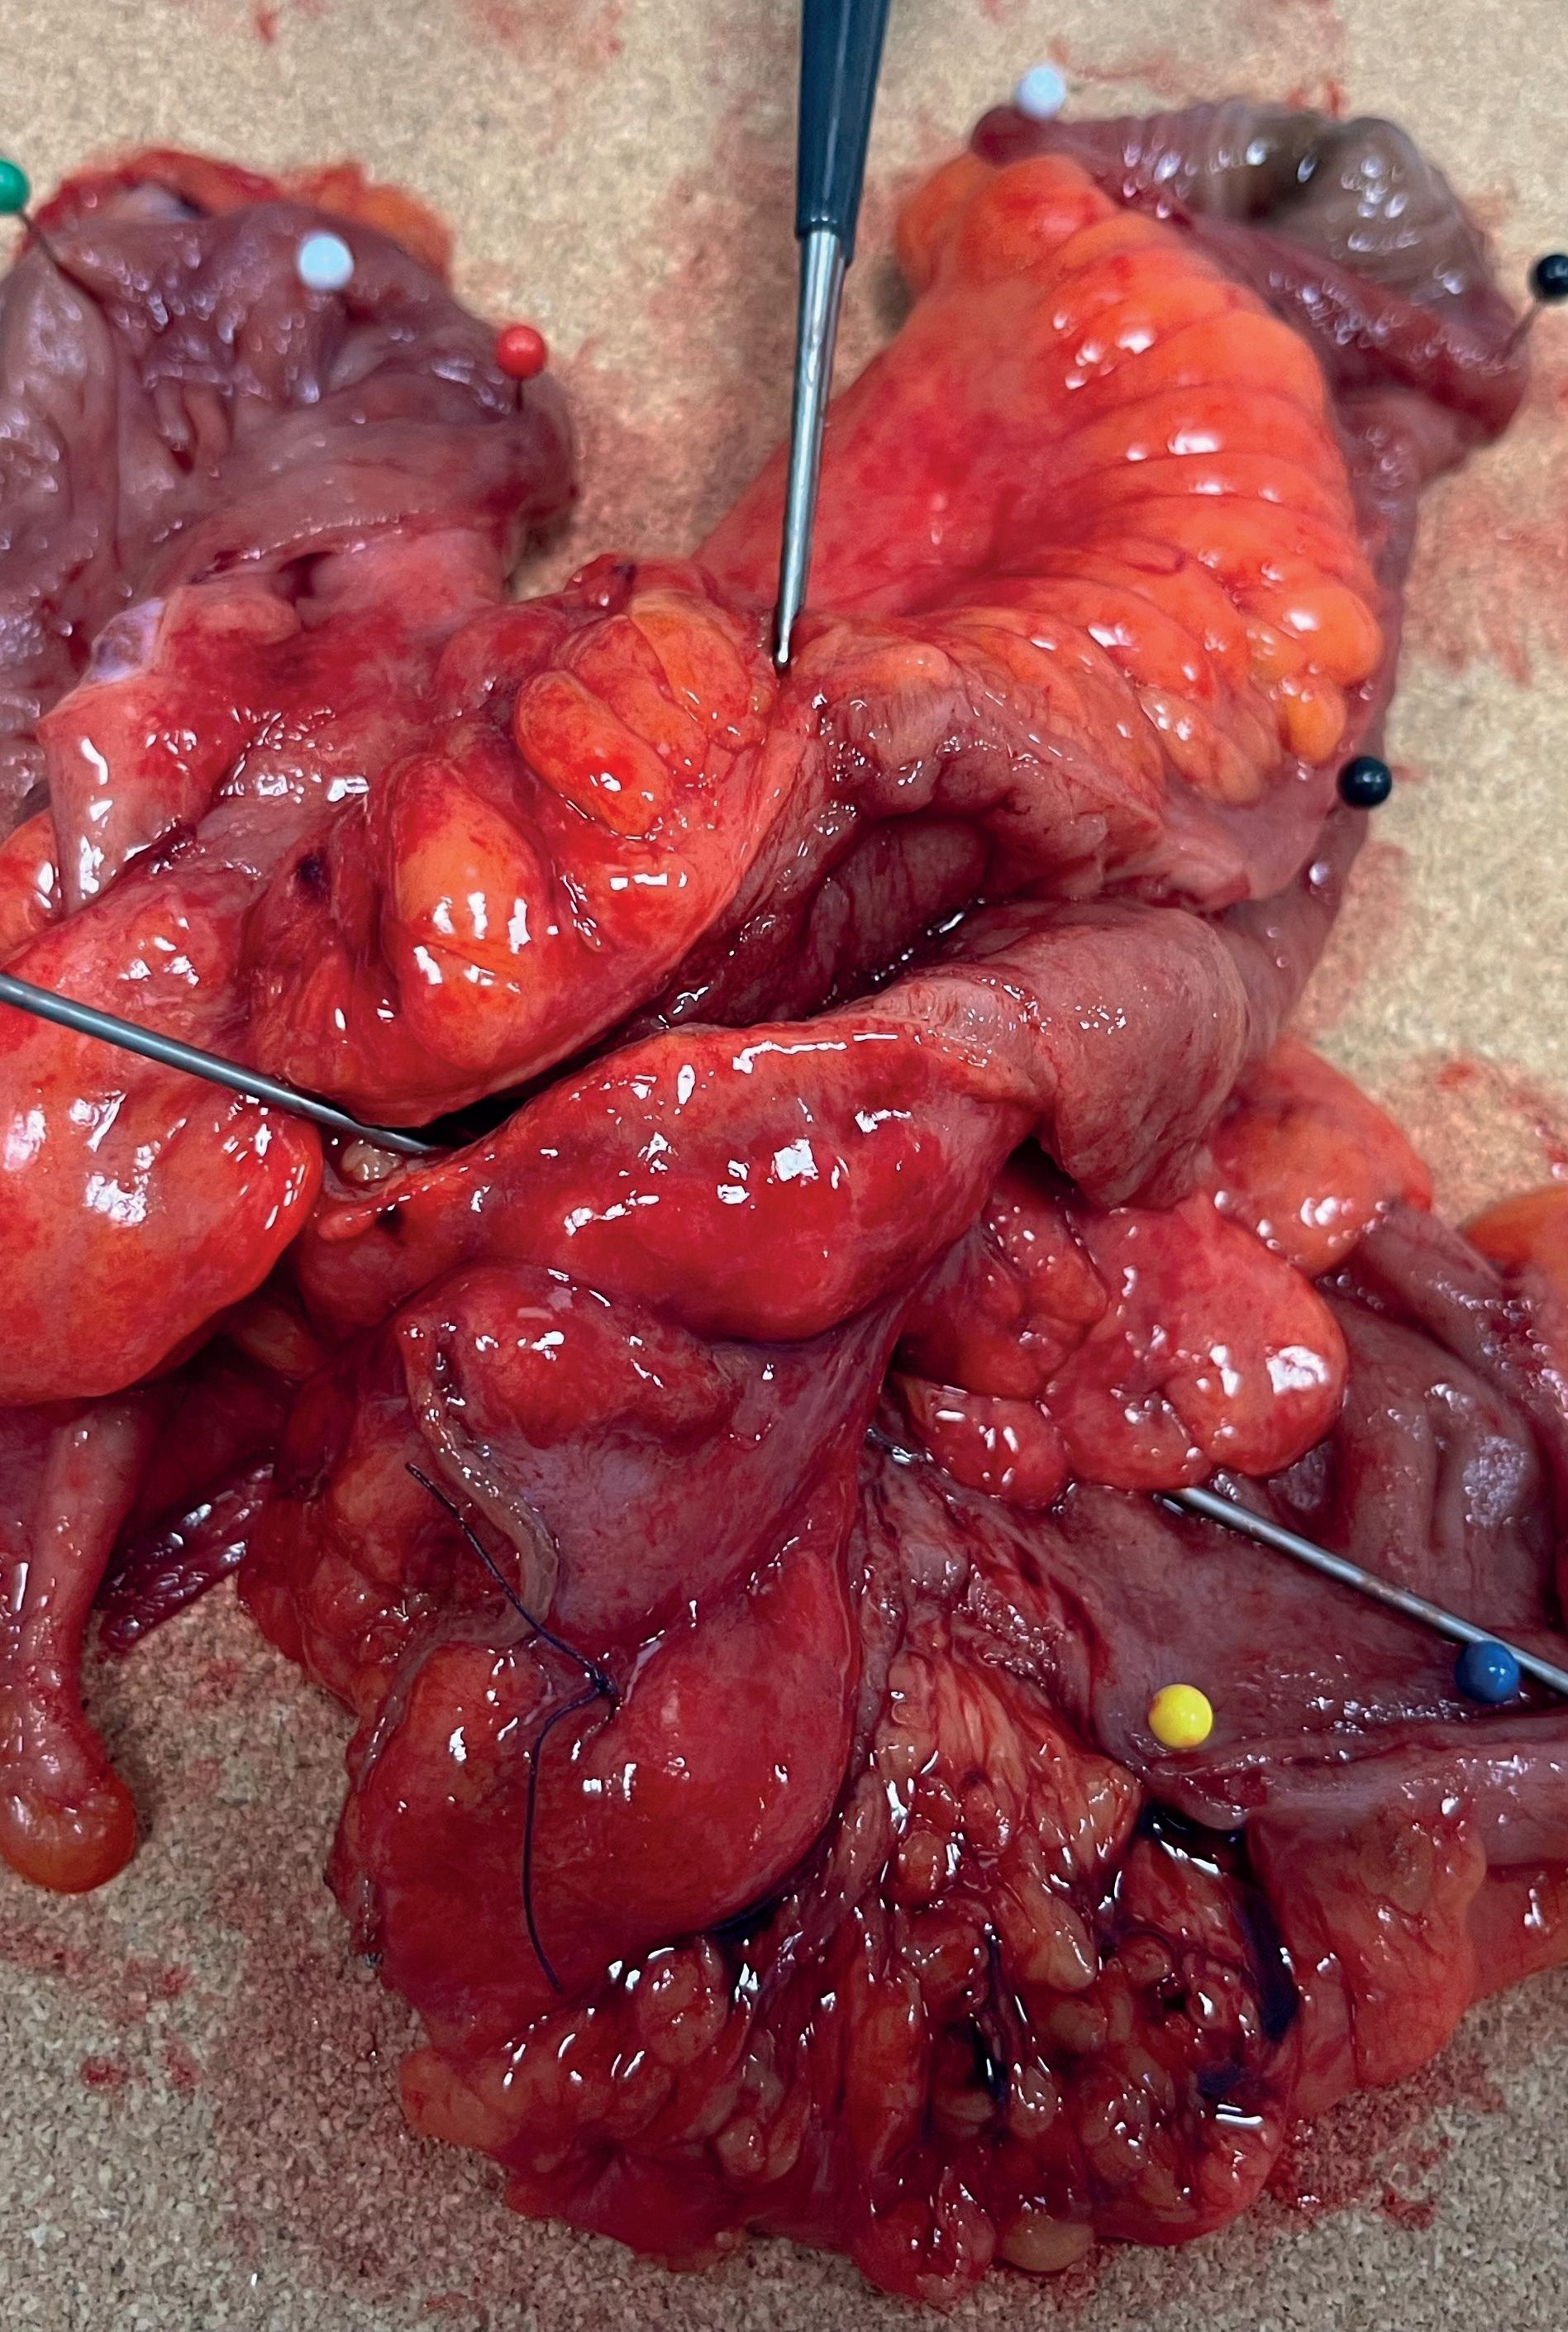

FIGUR 3: Crohns med betydelig fistulering. Det er anlagt multiple setoner som ledd i infeksjonskontroll før rektumamputasjon. Arkivbilde, tidligere samtykket til bruk i undervisningsøyemed.

Komplekse fistler

Komplekse fistler med bekken-, bløtvevs- eller organaffeksjon krever infeksjonskontroll som første tiltak. Drenasje med seton og abscessdrenasje inngår i dette. Definitiv kirurgi bør, som alltid ved Crohns, utføres først ved sykdomskontroll. Ofte er avlastende stomi nødvendig i kombinasjon med effektiv medikamentell Crohnsbehandling. Ved flere fistelganger med felles løp forsøkes disse forent der det er mulig. Separate løp kan behandles atskilt med spalting, fettvevstransplantasjon eller LIFT, tilpasset hver enkelt fistel. Før eventuell rektumamputasjon må infeksjonen være under kontroll og Crohns i remisjon (Figur 3). Ved større bløtvevsdefekter etter amputasjon kan rekonstruksjon og lappeplastikk i samarbeid med plastikkirurg være aktuelt, men dette er eget tema. Ernæring bør i tillegg optimaliseres.